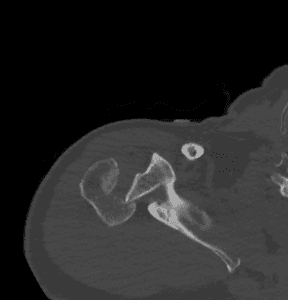

- Imaging:

- X-rays: Standard views to assess the fracture and dislocation.

- CT Scans: For detailed images.

- CT Angiography: Useful for identifying vascular structures in certain fracturepatterns.